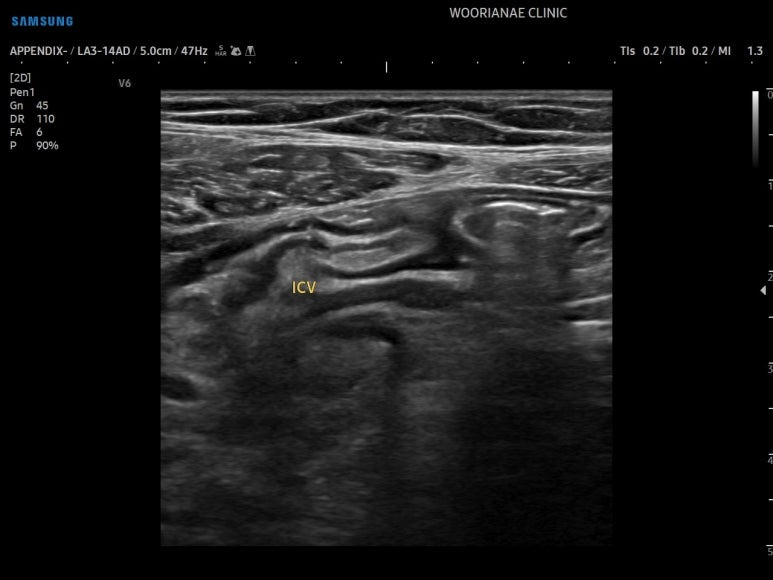

리니어 프로브로 관찰한 회맹판

정상 충수가 나오는 것의 확인